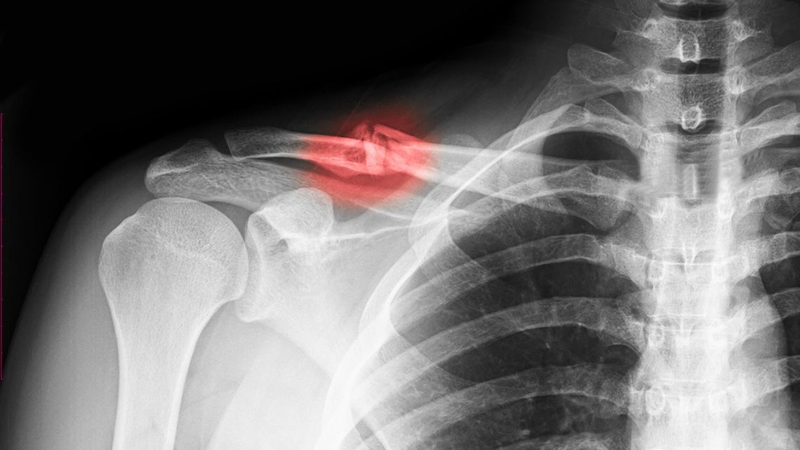

Gãy xương đòn là chấn thương thường gặp ở những người chơi thể thao, đặc biệt là bóng đá. Trong bài viết này, chúng ta sẽ cùng tìm hiểu thời gian hồi phục sau gãy xương đòn, những lưu ý quan trọng giúp đảm bảo an toàn nếu người bị chấn thương muốn quay lại đá bóng.

Bị gãy xương đòn bao lâu thì lành? Thời gian hồi phục sau gãy xương đòn không giống nhau ở mỗi người, phụ thuộc vào mức độ gãy và cách điều trị. Với trường hợp gãy nhẹ, không cần phẫu thuật, bệnh nhân thường hồi phục trong khoảng 6 - 12 tuần. Nhưng để trở lại các môn đối kháng như bóng đá thường cần khoảng 3 - 4 tháng (hoặc lâu hơn) cho tới khi có bằng chứng liền xương trên X-quang và phục hồi chức năng đầy đủ. Ở một số người được mổ cố định, thời gian trở lại có thể rút ngắn hơn, nhưng cần đánh giá cá thể hóa và xác nhận bởi bác sĩ và bác sĩ trị liệu. Ngoài ra, tuổi tác, thể trạng và việc tuân thủ phác đồ phục hồi chức năng cũng đóng vai trò quan trọng trong việc rút ngắn hay kéo dài thời gian hồi phục.

Một trong những nguyên tắc quan trọng nhất là không được bỏ ngang quá trình điều trị. Việc tự ý dừng thuốc hoặc ngưng tập phục hồi có thể khiến xương liền sai vị trí, làm giảm chức năng vận động. Gãy xương đòn đeo đai bao lâu? Bệnh nhân thường phải đeo đai trung bình từ 2 - 6 tuần, đến khi xương đòn bị gãy có can xương. Ngoài ra, người bệnh cần tái khám định kỳ để bác sĩ kiểm tra mức độ liền xương bằng X-quang hoặc thăm khám lâm sàng, từ đó điều chỉnh lộ trình phục hồi phù hợp.